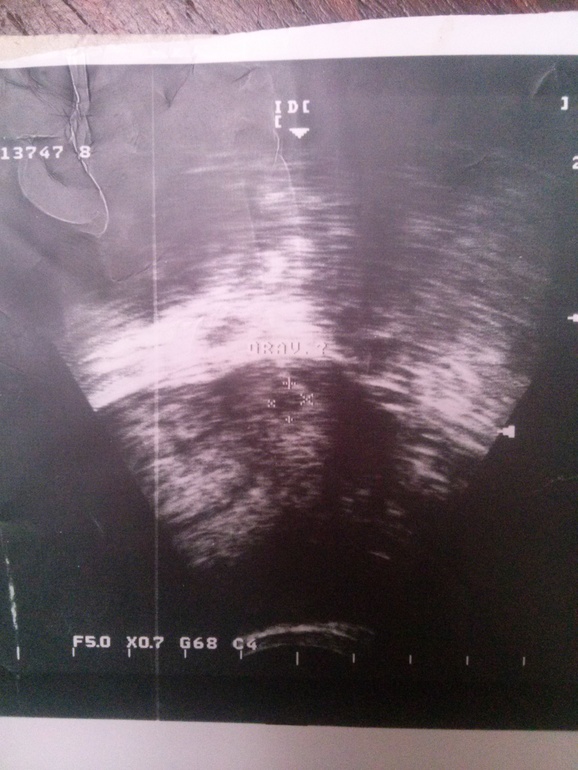

Этой фотографии уже больше 10 лет, это первое фото моего сыночка. Добавляю к себе в дневник, как приманочку. Ну, а для всех кому интересно: именно так выглядит плодное яйцо на второй день задержки. Тогда даже в описании к УЗИ написали плодное яйцо ? И еще по дате УЗИ, я сегодня высчитала, что оплодотворение тогда произошло именно в день О.(Это был день нашей свадьбы и я тогда все признаки О хорошо ощущала)